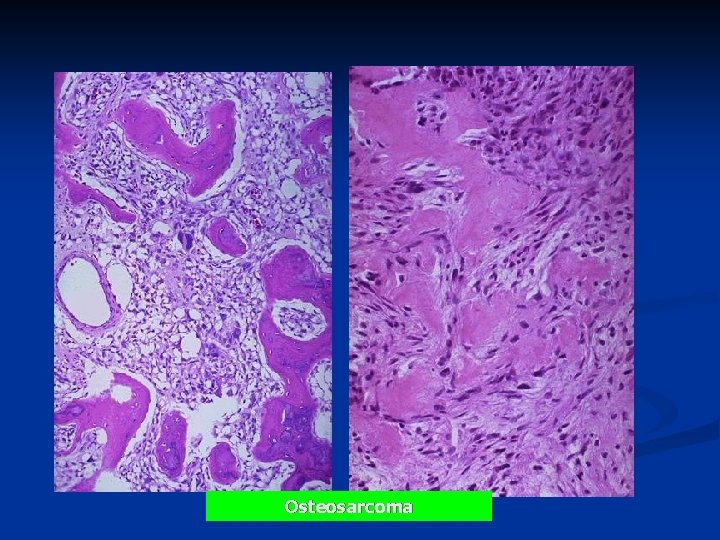

Microscopy n Proliferating malignant spindle- cell stroma n Osteoid or immature bone

Osteosarcoma

Osteosarcoma